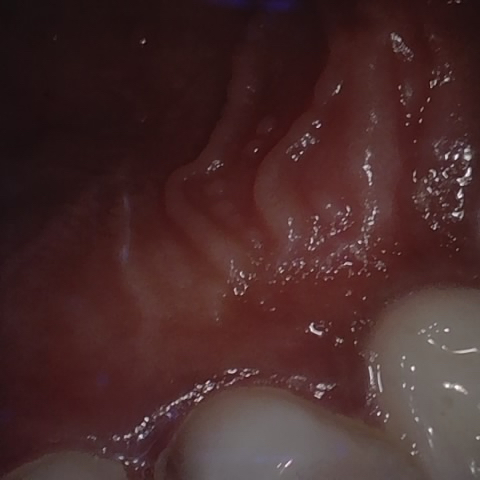

Incorrect Quality Level

The reference annotation for this image is

None

.

Please select the correct quality level.

Annotated as "Good"